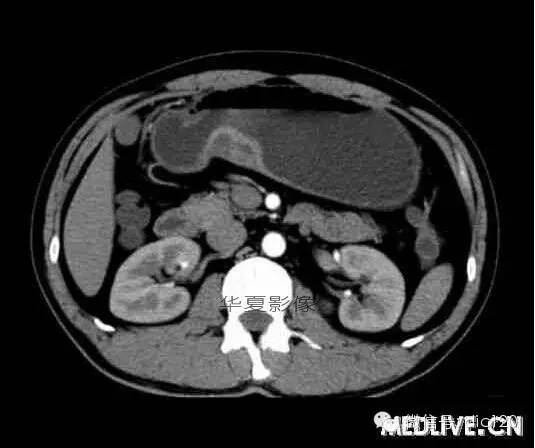

男,36歲,間斷性返酸噯氣3年,3個月前出現上腹疼痛,饑餓時加重。圖1-3為CT平掃,圖4-6分別為CT增強掃描的動脈期、門脈期和延遲期。

CT檢查可見胃幽門前區胃小彎側胃壁局限性增厚、隆起或伴凸向胃腔內的小結節灶,寬基地,境界光整,注射對比劑,增強掃描后,CT值可達50HU以上,與正常胰腺強化相仿。

胃迷走胰腺大多位在距幽門1-6cm的胃竇胃大彎側,粘膜下層內,為1-3cm大小的病灶。 與胃壁以寬基底相,增強掃描病灶表面覆蓋的黏膜明顯強化且連續,病灶內無明顯壞死,病變強化方式類似于正常胰腺組織;當病灶出現邊緣臍凹征或中央導管征時,對EP的診斷具有一定的特異性。